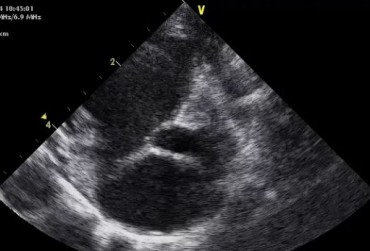

Zwężenie zastawki trójdzielnej jest jedną z form dysplazji pojawiającą się w różnym stopniu nasilenia (najczęściej łącznie z niedomykalnością zastawki) zarówno u psów, jak i u kotów. Cechami charakterystycznymi definiującymi zwężenie zastawki trójdzielnej są: obecność rozkurczowego wybrzuszenia (doming) płatków zastawki, zmniejszona ruchomość płatków, zmniejszona średnica ujścia zastawki. Mimo że zmiany morfologiczne aparatu trójdzielnego są typowe w przebiegu TVD i są znakiem rozpoznawczym tej choroby, nie są one zawsze bardzo silnie wyrażone i nie zawsze można mieć bezsprzeczną pewność diagnostyczną, bazując na badaniu echokardiograficznym [10]. Przypadki takie zdarzają się przede wszystkim u pacjentów, u których nie postawiono diagnozy we wczesnym etapie życia, a którzy pojawiają się na badaniu dopiero w starszym wieku z zaawansowanymi zmianami i niejednokrotnie z klinicznymi objawami prawostronnej niewydolności mięśnia sercowego i towarzyszącymi zaburzeniami w rytmie. W takich przypadkach obraz choroby może przypominać arytmogenną kardiomiopatię prawokomorową (arrhythmogenic right ventricular cardiomyopathy – ARVC) [1, 8]. Preekscytacja jest często obserwowana u ludzi z anomalią Ebsteina. U zwierzat, podobnie jak u ludzi, obecność dodatkowej drogi przewodzenia może nigdy nie prowadzić do rozwoju tachykardii nadkomorowej lub arytmia ta pojawiać się może dopiero w późniejszym okresie życia. Opisany przypadek jest przykładem pacjenta z dysplazją zastawki trójdzielnej i prawostronną niewydolnością serca będącą najprawdopodobniej konsekwencją tachykardii nadkomorowej.